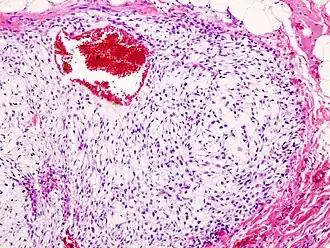

![]() Гистограмма хондромы стенки грудной клетки. Окрашено гематоксилином и эозином. | |

Хондросаркома — злокачественная опухоль хрящевого строения. Хондросаркома периферической локализации хорошо выявляется в виде плотной опухоли, прилегающей к кортикальному слою кости, иногда прорастающей в кость на различную глубину. В ней могут быть очаги оссификации и петрификаты. Опухоль плотноэластической консистенции, при наличии ослизнения, распада или кровоизлияний — более мягкая, не имеет ясного ограничения от соседней ткани. При разрезе нетрудно определить хрящевой её характер. При микроскопическом исследовании опухоль напоминает иногда хондрому, состоит из незрелых клеток с резко выраженным клеточным атипизмом. Часто рисунок опухоли имеет вид микросаркомы, в которой можно найти участки хрящевой ткани с плохо оформленными ячейками, содержащие неправильной формы хондробласты.